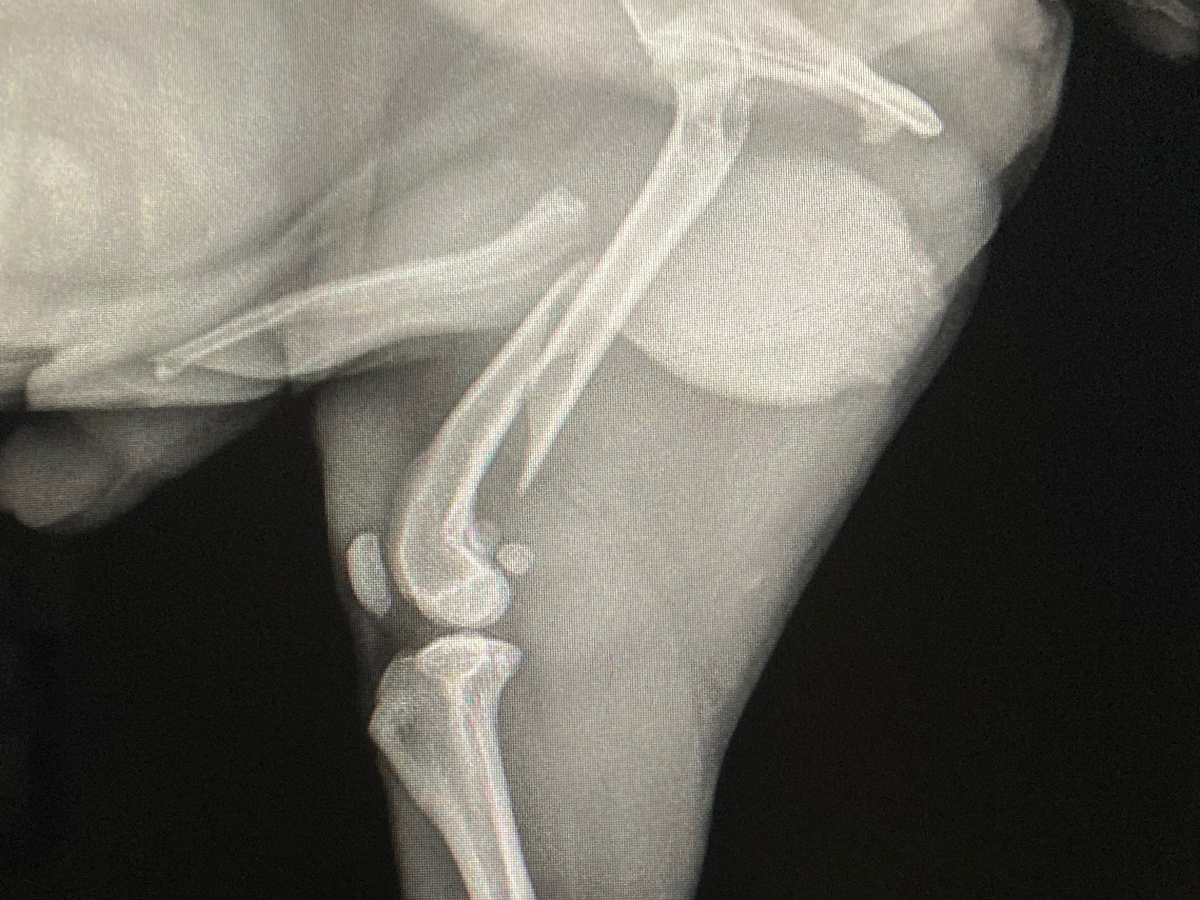

Update: 3:25a.m. Roscoe has a broken femur. His thigh is swollen and he’s given pain meds for now. Will need to take him to specialty hospital for a board certified surgeon evaluation in just a few hours. I’m told cost for surgery is between $8000 to $10,000, not including other miscellaneous fees. Either that I’m told to amputate his leg to save money. Seriously?!!! I’m all out of tears. I refuse to have his leg amputated because I don’t have the funds.

He lost his footing and fell today while he was on the couch and landed on his right hip. While we wait in the emergency room, he is whimpering in pain. His leg is bent the wrong way and I’m afraid to move it. He yelps when I tried to straighten it.